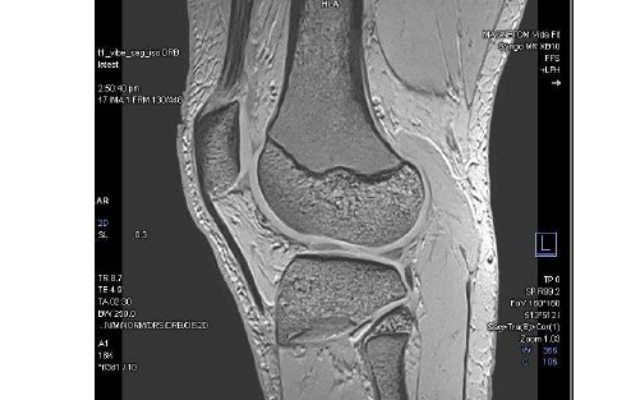

TRG Imaging’s Hawke’s Bay General Manager Paul Toomey said the new Canning Road clinic opening today includes a state-of-the-art $3m Siemens 3T MRI (magnetic resonance imaging) machine, supporting patients to receive world-class imaging resulting in earlier diagnosis and improved treatment pathways.